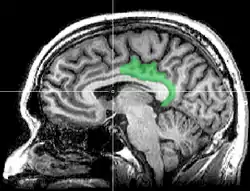

Sagittal MRI slice with highlighting indicating location of the posterior cingulate